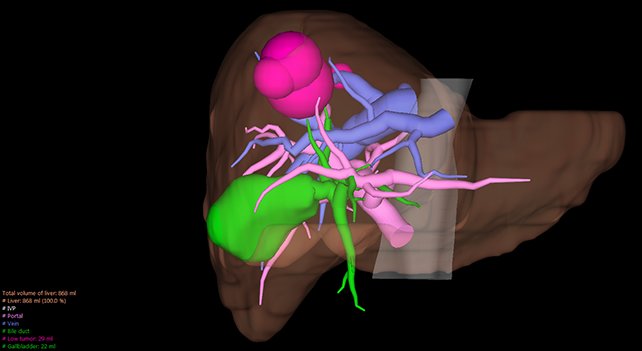

View X-Ray CT & MRI Scans Fast and Easily

Designed for surgeons, Pro Surgical 3D makes it easy to view patient scans quickly. Pro Surgical 3D facilitates the optimal 3D treatment and assessment workflows based on X-ray CT and MRI scans – and best of all, it’s FREE!

Everyone – including surgeons, patients and their loved ones – benefits from being better informed by the wealth of information buried within CT and MRI scans. Pro Surgical 3D gives surgeons more information to develop optimal treatment plans for patients. It also helps patients and their support group better understand their medical condition and proposed treatment options.

High-quality and fast 3D reconstruction and 3D rendering

Performs 3D reconstruction and volume rendering.

Instant and interactive surface extraction and export to STL and PLY formats.